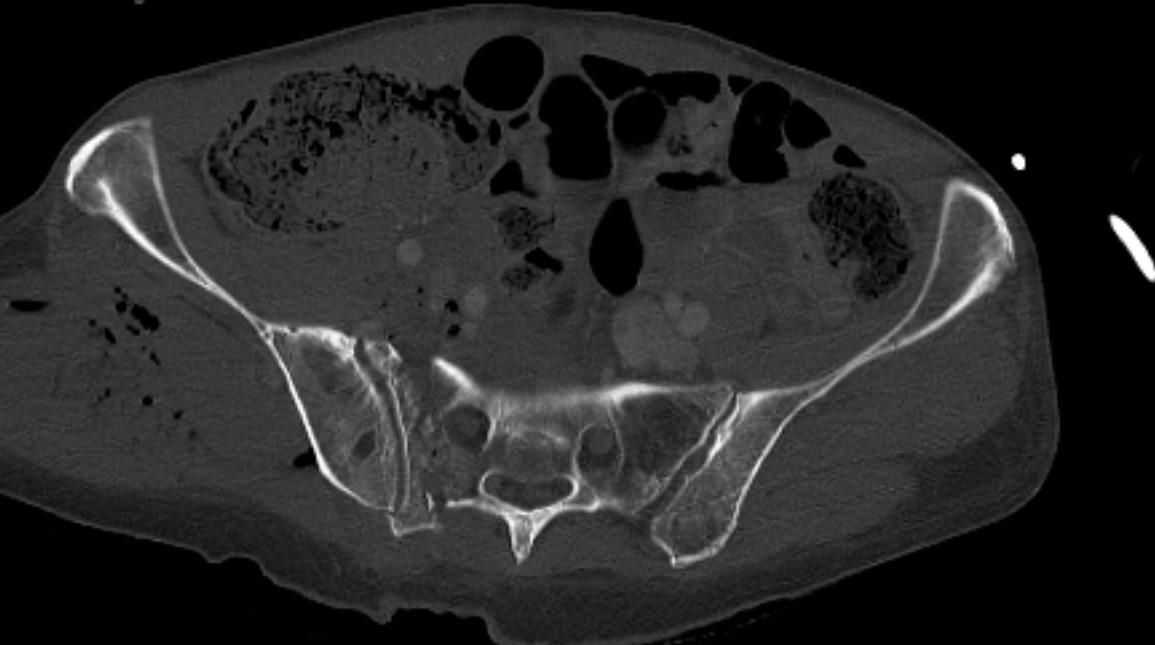

LC-1: pubic rami fracture with sacral fracture

Stability

Indications for EUA / lateral stress xray

- complete sacral fracture with pubic rami fractures

- internal rotation force

- look for displacement of pubic rami fractures